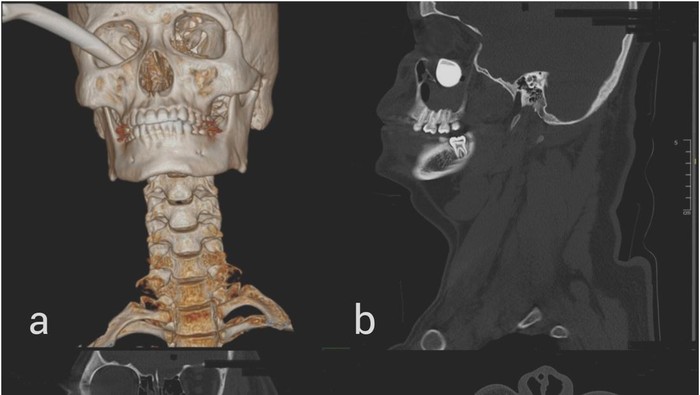

Seorang pria berusia 19 tahun terpaksa dilarikan ke unit gawat darurat (UGD) dengan ambulan setelah mengalami kecelakaan kendaraan bermotor. Dokter dari Universiti Malaya Eye Research Centre, Department of Ophthalmology, Universiti Malaya, Kuala Lumpur, Malaysia, mendapat informasi bahwa tuas rem sepeda motor harus dipotong oleh petugas pemadam kebakaran di lokasi kecelakaan karena tertancap di rongga mata kanan pasien.

Menurut laporan American Journal of Ophthalmology Case Reports, berjudul "When brakes fail you: Oculocardiac reflex elicited by a retained foreign body in a penetrating orbital injury", tuas rem sepeda motor berbahan logam tersebut 'nyangkut' di orbita inferior kanan melalui forniks konjungtiva inferotemporal.

Pria tersebut kemudian dilarikan ke ruang operasi darurat dan berhasil mengangkat tuas rem beserta jaringan yang rusak, menjahit lukanya dan memperbaiki kelopak matanya.

Tulang yang rusak di sekitar hidungnya juga diperbaiki dengan dua sekrup. Setelah benda asing tersebut dikeluarkan, denyut nadinya segera kembali ke kisaran normal dalam kisaran 72-80 denyut per menit.

Janji temu lanjutan enam bulan kemudian menemukan bahwa penglihatannya telah kembali normal. Kerusakan pada retinanya juga telah sembuh. Meski begitu, mata kanannya masih tampak sedikit cekung sekitar 5 mm dan pria tersebut menolak perawatan lebih lanjut.